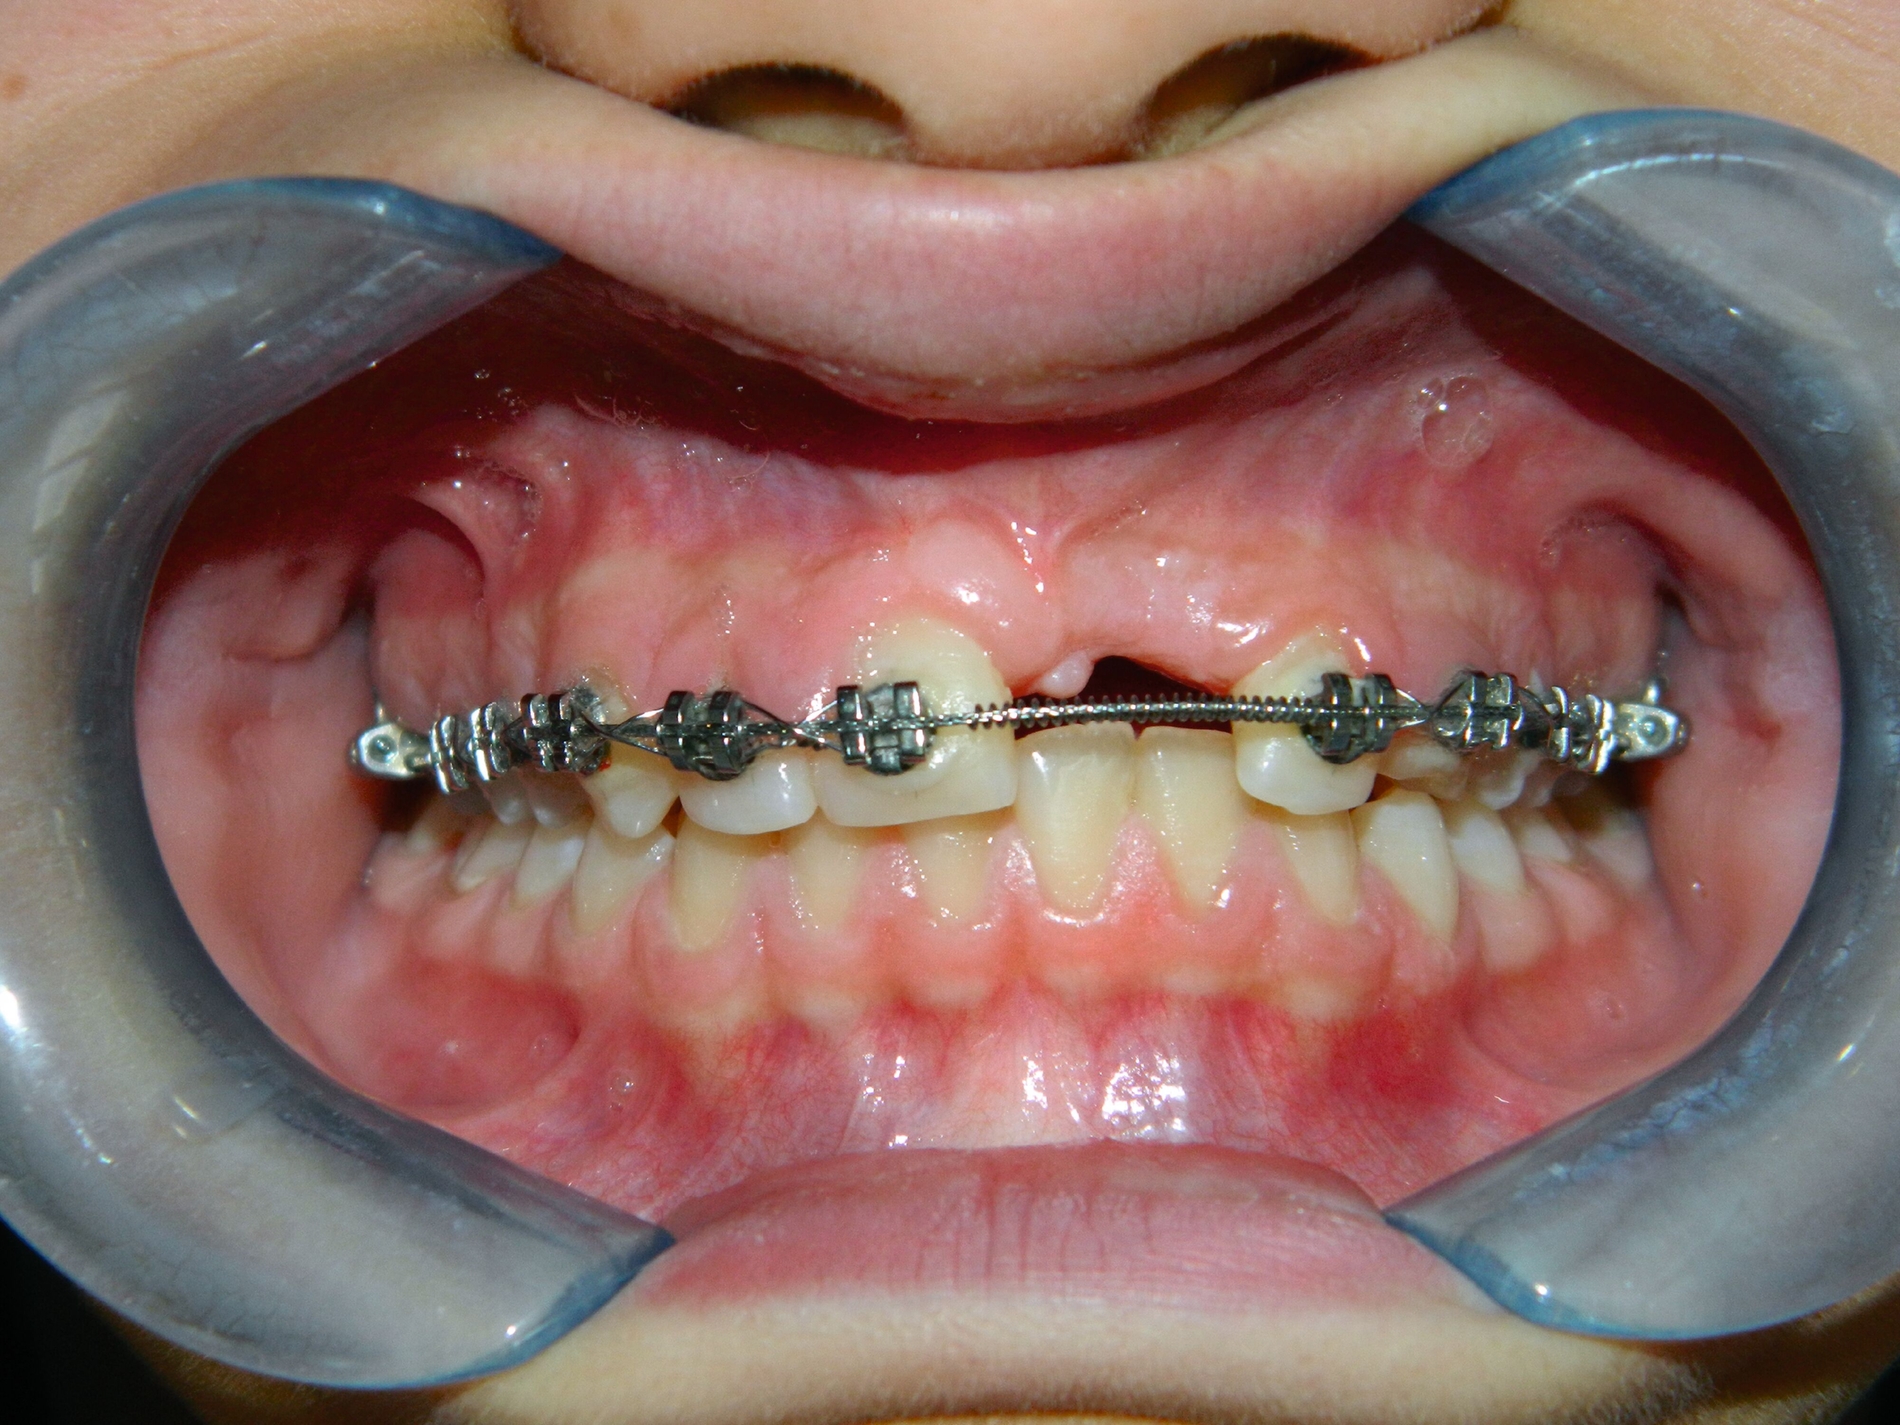

Im Februar 2019 wurde die kieferorthopädische Klinik von der Erstautorin übernommen. Bei der Auswertung der vorgefundenen Daten der Patientin wurde festgestellt, dass der linke obere zentrale Schneidezahn vor sechs Monaten extrahiert worden war. Die festsitzende Apparatur war im Oberkiefer bereits eingegliedert. Die Druckfeder zwischen Zahn 11 und 22 diente zur Lückenöffnung für den späteren prothetischen Ersatz des Zahnes 21. Auch auf den persistierenden linken Milcheckzahn war ein Bracket geklebt. Die Okklusion im Bereich der ersten Molaren war rechts und links neutral (Abbildung 2).

Um die Position des impaktierten Eckzahns zu beurteilen, wurde zehn Monate nach der Extraktion des Schneidezahns eine weitere Panoramaröntgenaufnahme angefertigt, Die Position des Eckzahns war unverändert, jedoch hatte die Extraktion des impaktierten oberen Schneidezahns zu einer signifikanten Knochenresorption und Atrophie des Alveolarkamms (Abbildung 3) geführt.